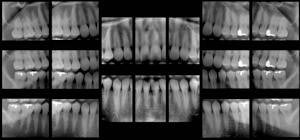

Top, standard panoramic image from a PC-1000 system using a CdTe sensor from Ajat and the PanoACT-1000 tomosynthesis software. Middle, although the anterior teeth are distorted, the posterior teeth no longer have overlapped interproximals. By manually positioning the patient in the system, the contacts are now open. Bottom, the tomosynthesis software then autocorrected the image to bring the front teeth into focus. All images courtesy of Dr. Robert Langlais. |

"In ordinary digital imaging, the software can make the image lighter or darker, change the contrast, magnify, zoom, copy, etc.," he said. "This software goes beyond that. It will autocorrect for positioning errors and generate a new image that is better than the original image. This is a software function that other digital imaging software just can't do."

In addition, the software can take a single panoramic x-ray and automatically divide it up to display as a full-mouth intraoral survey, extracting 18-20 regions of interest from a single pano image. This opens up the possibility of using this technique for posterior interproximal caries detection, he added.

"Everyone in the dental profession believes that the bitewings are the gold standard for finding cavities between the back teeth," Dr. Langlais said. "Panoramic images overlap the contact points and don't provide as much detail as the intraoral bitewing images. But in tomosynthesis, we've experimented with getting the patient into a position where the interproximal contacts are open. We have been successful in taking a [pano] machine and acquiring the whole scan with the contacts open."